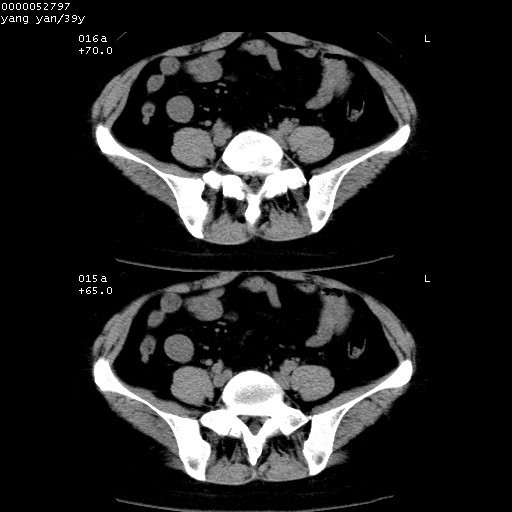

患者 女,39岁。因外伤检查,偶然发现。

典型!双侧骶髂关节致密性骨炎。

病变累及髂骨关节面,腰椎椎小关节结构紊乱,不除外强直性脊柱炎,建议结合实验室检查

典型!病变主要累及双侧髂骨。常见于育龄期妇女。

致密性骨炎,一般不跨越关节面,可是这个骶骨关节面也有硬化。

髂骨致密性骨炎系一种以骨质硬化为特点的非特异性炎症,有高度致密的骨硬化现象,尤其以髂骨下2/3更为明显,但关节间隙则无改变。因位于骶髂关节,且该关节症状明显,故又称之为“骶髂关节致密性骨炎”。 本病90%以上为中年女性,以妊娠后期、尤其分娩后为多见,亦可见于尿路或女性附件慢性感染后,或盆腔内其他感染。此外,臀骶部的外伤亦可诱发或引起本病。  妊娠、分娩及外伤均可引起骶髂关节韧带的撕裂而易使局部的血供受阻。因此早期局部呈现充血、水肿及渗出增加等,渐而局部出现增生与变性反应,随着胶原纤维的致密化而向硬化演变;血管形成厚壁血管,易闭塞而引起髂骨耳状面处缺血和缺氧,骨质呈现硬化性改变,以致手术时局部出血较少。骶髂关节囊壁显示纤维增生、弹性降低及松动样改变。继发于盆腔内炎症者亦出现相类似的病理改变,可能系细菌内毒素作用所致。